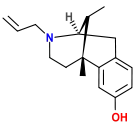

Oripavine derivatives

- Buprenorphine—partial agonist

- Dihydroetorphine

- Etorphine